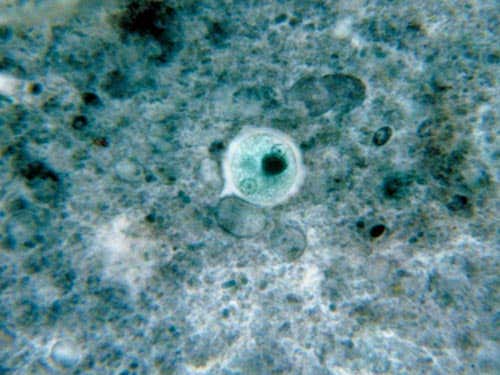

Entamoeba histolytica

This single-celled organism causes a disease called amoebiasis.

It predominantly infects humans and other primates.

It can be found in water, damp environments and in soil, and can contaminate fruits and vegetables.

It spreads through faecal contamination.

Other than the malarial parasite, it causes more deaths than any other protozoan.

Symptoms: abdominal pain, weight loss, weakness, diarrhoea, liver abscess

(Image: CDC / George Healy)